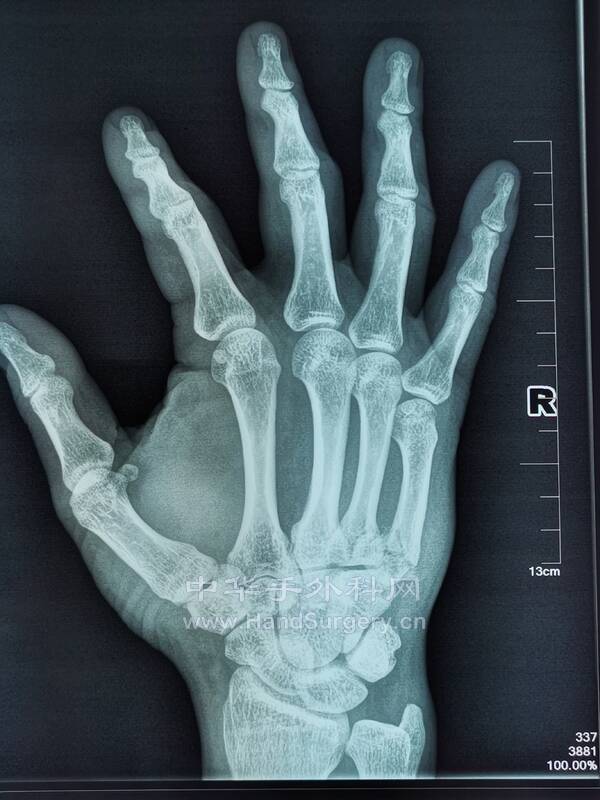

微信图片_20220614224346.png

微信图片_20220614224350.png